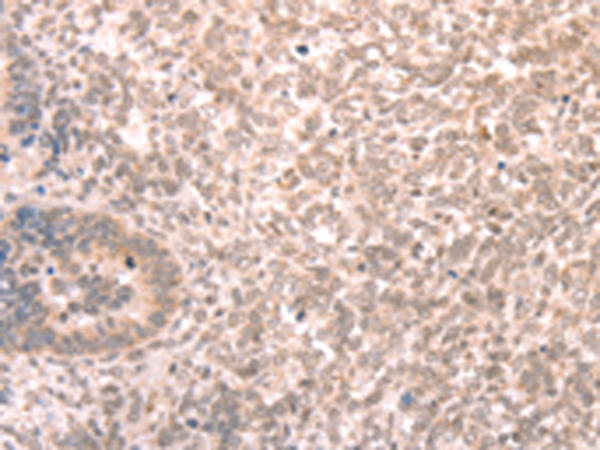

分类: 科研抗体货号: P11158别名: Fz-3应用: IHC反应种属: Human, Mouse